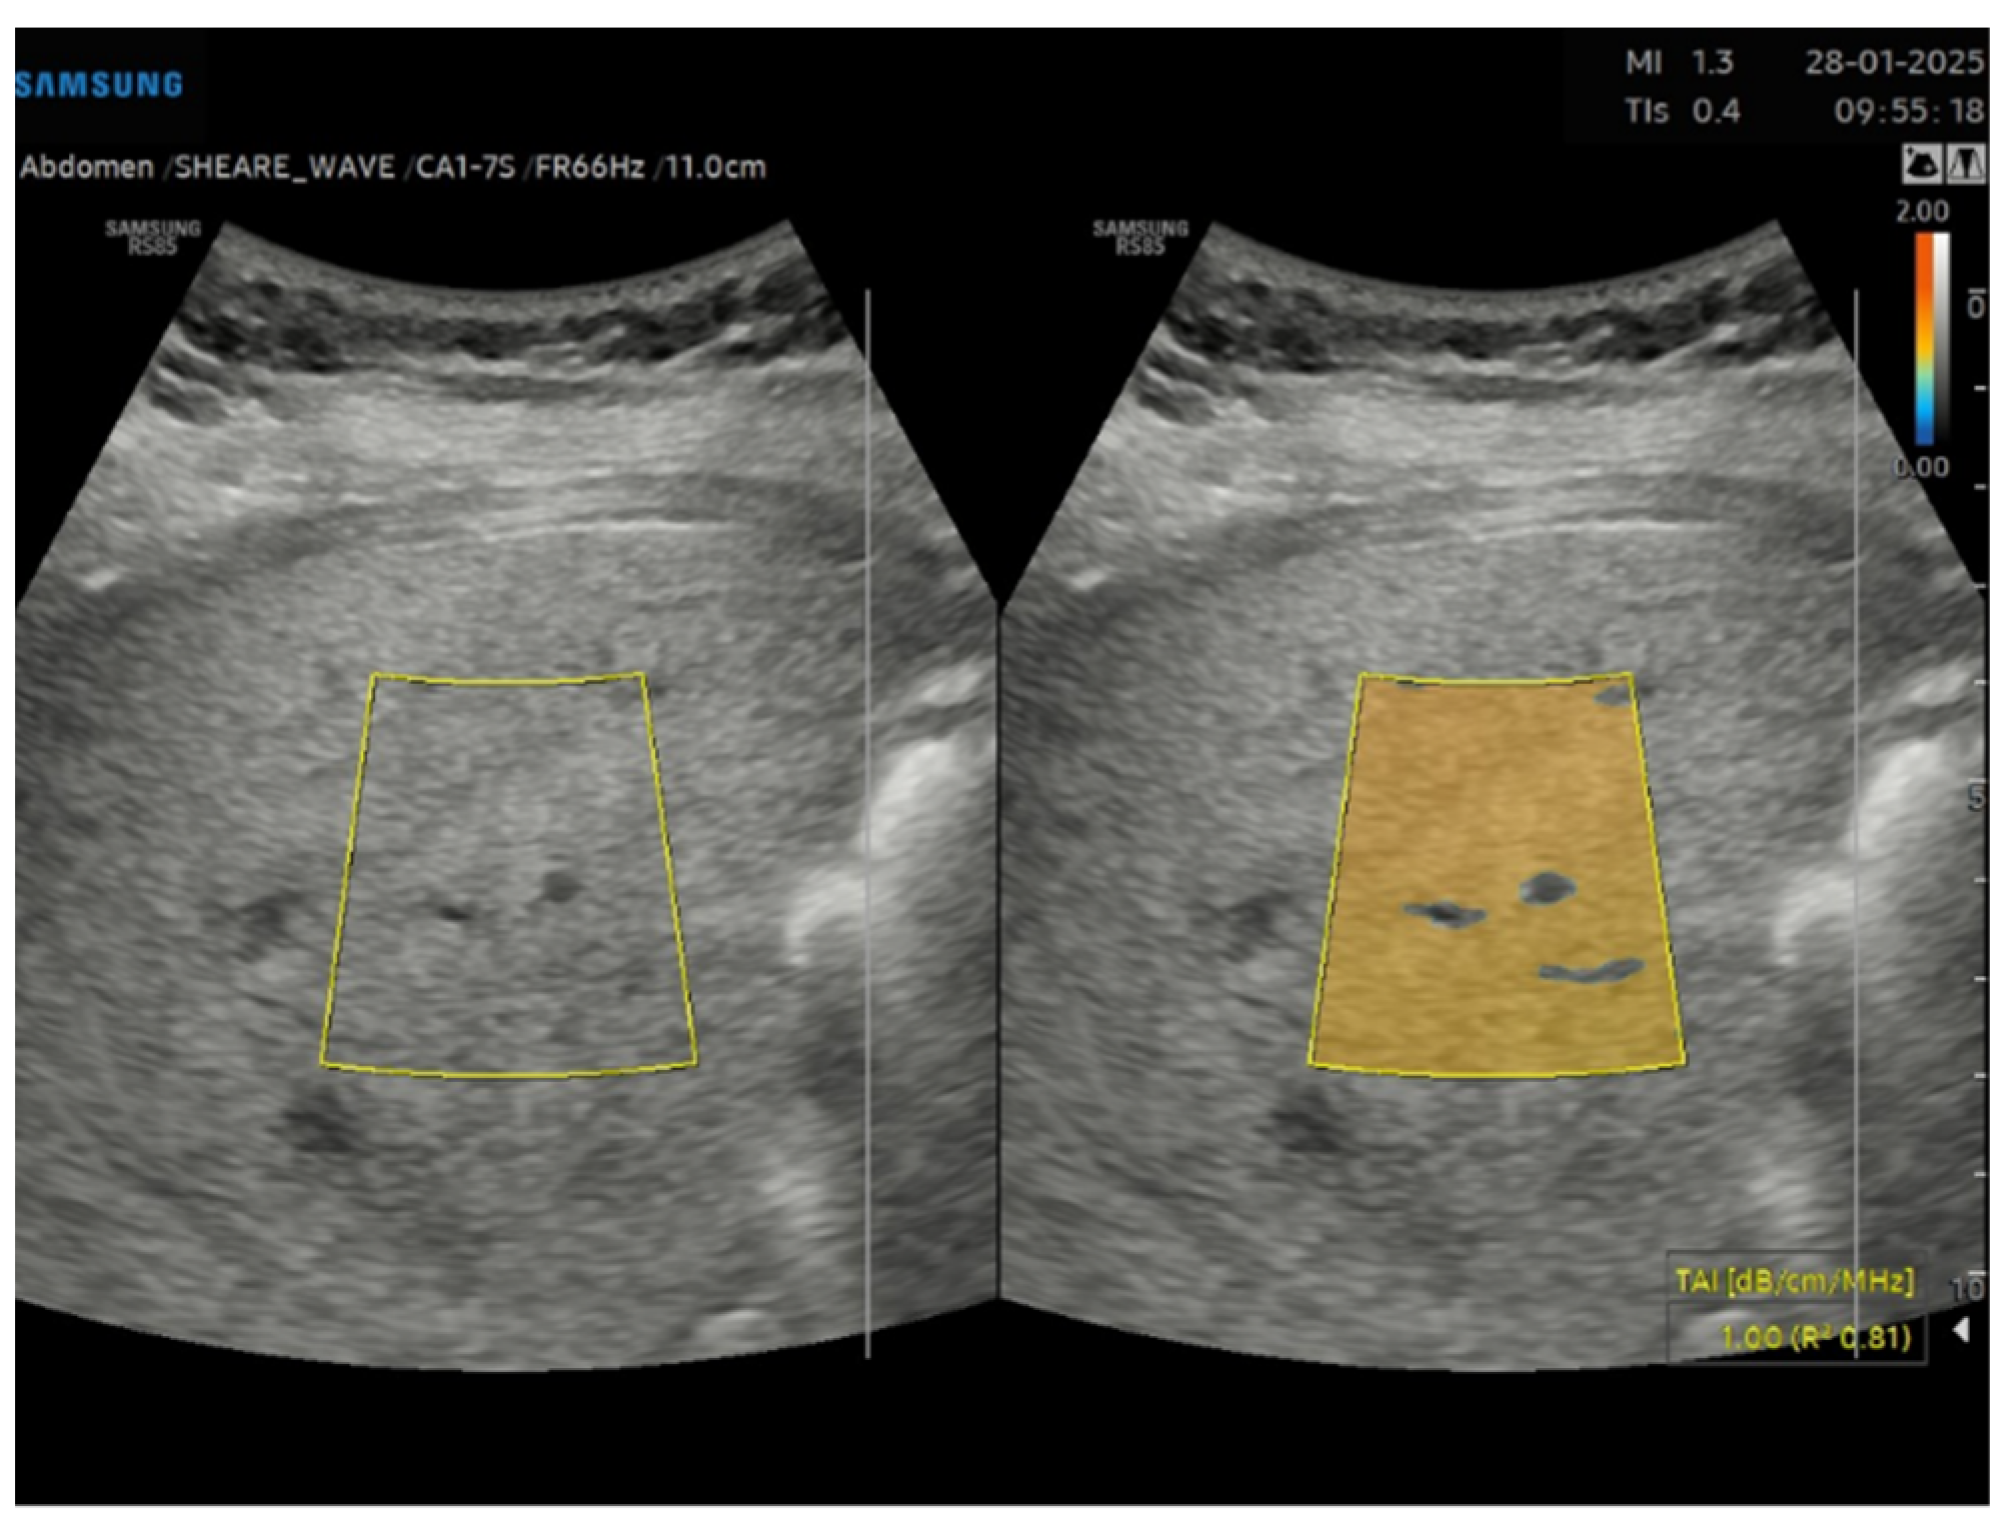

Figure 3. Tissue attenuation imaging (TAI) of a steatotic liver (S3) in a 33 years old male patient with grade III obesity.

Among non-invasive alternatives, magnetic resonance imaging-based proton density fat fraction (MRI-PDFF) is an accurate and reproducible method for quantifying liver fat and has been used as a reference standard in numerous clinical trials [16,17]. Despite its precision, MRI-PDFF lacks cost-effectiveness for widespread clinical use. In this context, recent studies have demonstrated promising results for detecting and grading hepatic steatosis using US and quantitative ultrasound (QUS), which combine non-invasiveness, broad availability, and cost-effectiveness [18,19]. Fat deposition alters ultrasound signals in three key ways: amplitude, frequency variation, and signal scattering. The brightness information in US images reflects a combination of these properties. Several methods have been introduced to quantify these changes and improve the diagnosis of fatty liver. One of these tools is the echogenicity ratio of the liver compared to the kidney, namely hepato-renal index (HRI). HRI has shown significant correlation with histologic steatosis. Studies have reported that HRI is highly accurate (>90%) for detecting hepatic steatosis and correlates strongly with MRI-PDFF in patients without advanced liver fibrosis [20]. Currently, several US manufacturers offer automated HRI calculation tools. In particular, Samsung offers as a quantification tool for fatty liver the EzHRI function which improves workflow by suggesting initial ROI (region of interest) positions. Moreover, other techniques used in clinical studies estimate the attenuation coefficient (AC) and the backscatter coefficient (BSC). The AC measures the loss of US energy in tissue, whereas the BSC measures the US energy reflected from tissue, which relates to tissue microstructure [21]. Samsung has integrated these methods into their US systems, proving tools like TAI (Tissue Attenuation Imaging) and TSI (Tissue Scatter Imaging). TAI quantitatively measures the attenuation of ultrasound signals received from the liver. TSI quantifies the scattered signal distribution based on backscattered signals. The combination of AC and BSC allows for the calculation of the ultrasound fat fraction (USFF), a quantitative US-based method for estimating liver fat content [22]. Several studies have shown strong agreement between USFF and MRI-PDFF measurement for quantifying liver fat content, highlighting its potential clinical utility in enhancing the diagnostic value of US for hepatic steatosis [23,24]. Despite this advancement, there is limited data regarding the clinical use of USFF, and threshold for different grades of steatosis remains undefined. Nonetheless, none of the previous study investigating the diagnostic value of the USFF, focused on the subset of obese patients, which is a major risk for evolution from MASLD to liver cirrhosis [25]. Additionally, due to the technical challenge to perform a good quality imaging in obese patients, a reliable non-invasive standard measurement of liver steatosis could be crucial [26].

This is a cross-sectional observational study based on retrospectively collected ultrasound and clinical data. A total of 95 obese patients who underwent abdominal ultrasound examination as part of the preoperative assessment for potential bariatric surgery between November 2023 and April 2024 were evaluated. Ultrasound examinations were performed by expert echographers (with a minimum of 5 years’ experience in abdominal US) using Samsung RS85 Prestige system. The examination was performed after at least 6 h of fasting, with the patient in the supine position, using a right intercostal scanning approach. Each patient underwent conventional abdomen ultrasound with visual assessment of liver steatosis (Figure 1) and subsequently to the measurement of USFF with the Samsung CA1–7S (1 MHz–7 MHz) transducer. The ultrasonographic steatosis visual assessment and the USFF measurement were performed by different groups of operators in a blinded manner. TSI (Figure 2) and TAI (Figure 3) data were acquired and subsequently processed using proprietary algorithms developed and calibrated at the Samsung Medical Center [27,28]. These algorithms extracted relevant parameters, namely the attenuation coefficient and backscatter coefficient. A mathematical model grounded in established physical principles and incorporating empirical data, was then employed to translate these extracted parameters into an estimate of the liver USFF. Patients with clinical or morphological features of advanced liver diseases or cirrhosis, active viral hepatitis, alcohol use disorder, altered liver enzymes and heart failure were excluded. The collected data included age, gender, body mass index (BMI), TAI, TSI, USFF values, liver enzymes, comorbidities.